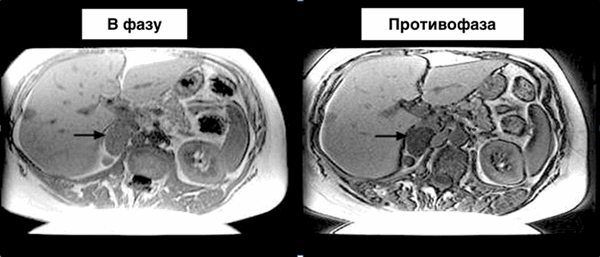

- МРТ: значительное снижение ИС на противофазном Т1-ВИ (за счет интравоксельных липидов и воды)

(Справа) Бесконтрастная КТ: у мужчины 45 лет выявлено гомогенное поражение левого надпочечника низкой плотности (ОНИ) размером 2 см. В последующем была выполнена МРТ, однако методом выбора для описания образований надпочечника обычно служит бесконтрастная КТ. (Слева) МРТ, синфазное Т1-ВИ: у этот же пациента выявлено четко отграниченное поражение левого надпочечника с умеренной ИС.

(Справа) МРТ: на соответствующем противофазном Т1 -ВИ выявлено равномерное подавление сигнала от левого надпочечника. Низкая плотность (менее 10 HU) на бесконтрастной КТ и выпадение сигнала на МРТ с химическим сдвигом-характерные черты аденомы с высоким содержанием липидов.б) Дифференциальная диагностика:

2. MPT-протокол для визуализации надпочечников. Аденома надпочечника с высоким содержанием жира может быть выявлена с помощью Т1 -ВИ в последовательности градиентного эха, которая включает как синфазное, так и противофазное построение изображения. Потеря сигнала от образования надпочечника на противофазном изображении по существу служит диагностическим критерием аденомы. Аденомы с низким содержанием жира можно не определить на МРТ, они лучше всего могут быть оценены с помощью КТ-протокола для визуализации надпочечников.

(Справа) Оценка повышения уровня кортизола или адреналина также служит определяющим фактором в диагностике образований надпочечники. (Слева) На синфазном Т1-ВИ в последовательности градиентного эха у пациента с двусторонними узелками или опухолями небольших размеров в надпочечниках достоверно выявлен узел только в левом надпочечнике.

(Справа) На Т1-ВИ в последовательности градиентного эха у этого же пациента выявлено выпадение сигнала от узелков в надпочечнике, что указывает на сочетание липидов и протонов воды. Это служит характерным признаком аденомы с высоким содержанием липидов.3. Все ли опухоли надпочечника, содержащие жир, — аденомы? Аденомы редко содержат макроскопический жир. Липиды в аденомах надпочечников представлены микроскопическим жиром, а наличие макроскопических отложений жира характерно для менее распространенного новообразования надпочечника-миелолипомы (не путать с почечной ангиомиолипомой, отличающейся во всех отношениях). Миелолипома - редкая доброкачественная опухоль надпочечника, которая, как правило, может быть точно диагностирована на КТ или МРТ при наличии отложений зрелой жировой ткани с наличием или без кальцификатов или мягкотканных элементов.

Методика МРТ сканирования:

- В и противофазу T1-GRE-в аксиальной и коронарной плоскости.

- HASTE (SSFSE) T2-изображения в аксиальной и коронарной плоскости.

- T1 FS GRE

- Постконтрастные T1FS

Наибольшее значение имеют изображения в фазу и противофазу так, как по ним возможно отдифференцировать аденому от злокачественного новообразования.

- Отношение сигнала от надпочечника к селезенке (ОСНС)=(ROI от аденомы/ROI от селезенки в противофазу)/(ROI от аденомы/ROI от селезенки в фазу)

- Индекс интенсивности сигнала от надпочечника (ИИСН)=(ROI от аденомы в фазу - ROI от аденомы в противофазу)/(ROI от аденомы в фазу).

- Отношение сигнала от надпочечника к селезенке (доброкачественное образование)

- Индекс интенсивности сигнала от надпочечника (>5%=>доброкачественное образование)

- ОСНС=(31/120)/166/119)=0,25/1,39=17,9%

- ИИСН=(166-31)/166=81%